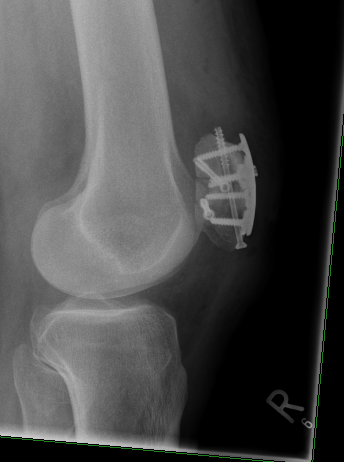

Blöderweise bin ich mit dem rechten Bein irgendwie am Rad hängengeblieben und nicht auf den Asphalt, sondern das Rad gefallen. Konsequenz: offener Trümmerbruch in der Kniescheibe. Aua!

Wurde noch am gleichen Tag von Spezialisten der BG Unfallklinik in Frankfurt operiert. OP ist wohl gut gelaufen, bislang ist von Infektion keine Spur, und die wirklich beeindruckende Kniewunde heilt bislang ok.

Hier der Vorher-Nachher-Vergleich.